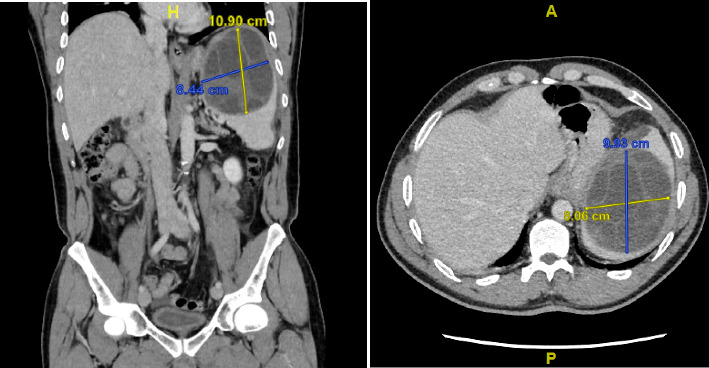

Introduction: Cystic echinococcosis, also known as hydatid cyst, is a parasitic infection of mammals that can affect any organ. Although the diagnosis of primary splenic echinococcosis is challenging, especially in nonendemic areas, it can be life-saving because an anaphylactic shock may occur when the cyst ruptures. Recommendations regarding optimal treatment options after rupture are scarce, and the overall prognosis remains poor. Case Presentation: A patient with a spontaneous rupture of an isolated splenic hydatid cyst was treated with splenectomy and peritoneal lavage with a hypertonic salt solution. The patient survived despite rapidly progressive hypernatremia, which was treated with conventional therapy along with continuous venovenous hemofiltration with gradient sodium replacement. Discussion: When the decision is made to treat a patient with a spontaneously ruptured splenic echinococcus cyst, splenectomy is the only surgical option. Hypernatremia is a complication to be expected when hypertonic saline is used to rinse the splenic and abdominal cavities. Conclusion: This case highlights the importance of prompt surgical intervention and the management of hypernatremia in patients with ruptured splenic hydatid cysts.